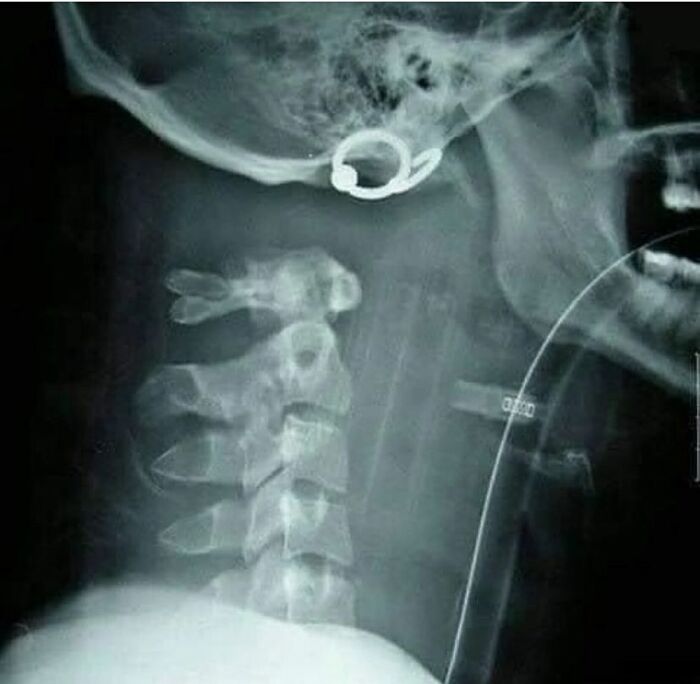

Quiso tomarse sus dosis de medicamentos de una con todo y blíster